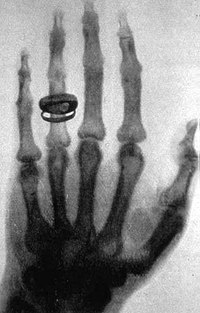

A primeira radiografia da história ocorreu em 22 de dezembro de 1985. Neste dia, o físico Roentgen pediu uma ajuda à sua esposa, Anna Bertha Roentgen, posicionando a mão dela no chassi. Utilizando filme fotográfico ele fez com que a radiação incidisse ali, por cerca de 15 minutos.

Quando ele revelou o filme, suas suspeitas foram confirmadas: ele pôde visualizar a figura da mão da esposa por dentro, com todos os ossos e as partes menos densas devidamente mapeadas: